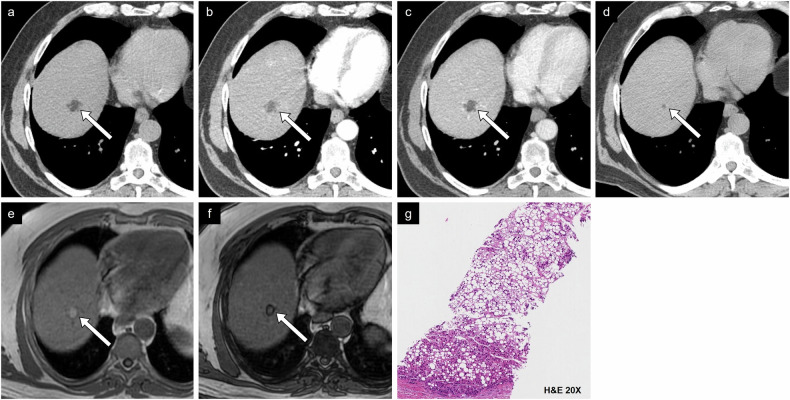

Fig. 11.

Case example of non-proliferative imaging features. HCC in a 73-year-old man with metabolic dysfunction-associated steatotic liver disease. a Non-contrast CT image shows a small lesion measuring 2.3 cm between segments VII and VIII with density compatible with macroscopic intralesional fat. b Arterial phase and (c) portal phase images show a hypodense lesion. d On CT performed 2 years prior, the lesion measured 0.6 cm on the non-contrast phase, corresponding to threshold growth. e In-phase and (f) out-of-phase MR images show a drop in signal in out-of-phase imaging. g Histologic examination showed a well-differentiated HCC of steatohepatitic type. H&E, hematoxylin and eosin